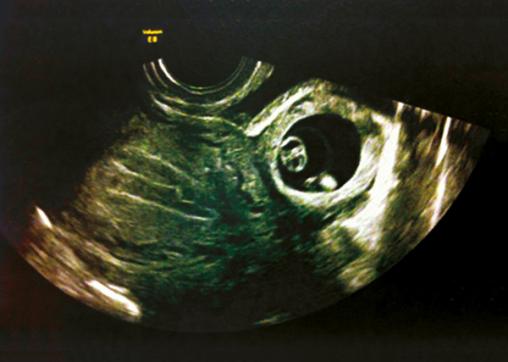

Grossesse extra-utérine : signe direct

Masse embryonnée latéro-utérine.